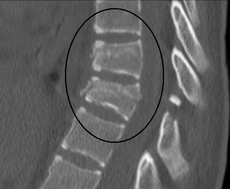

compresssion fracture

chance francture

from seatbelt